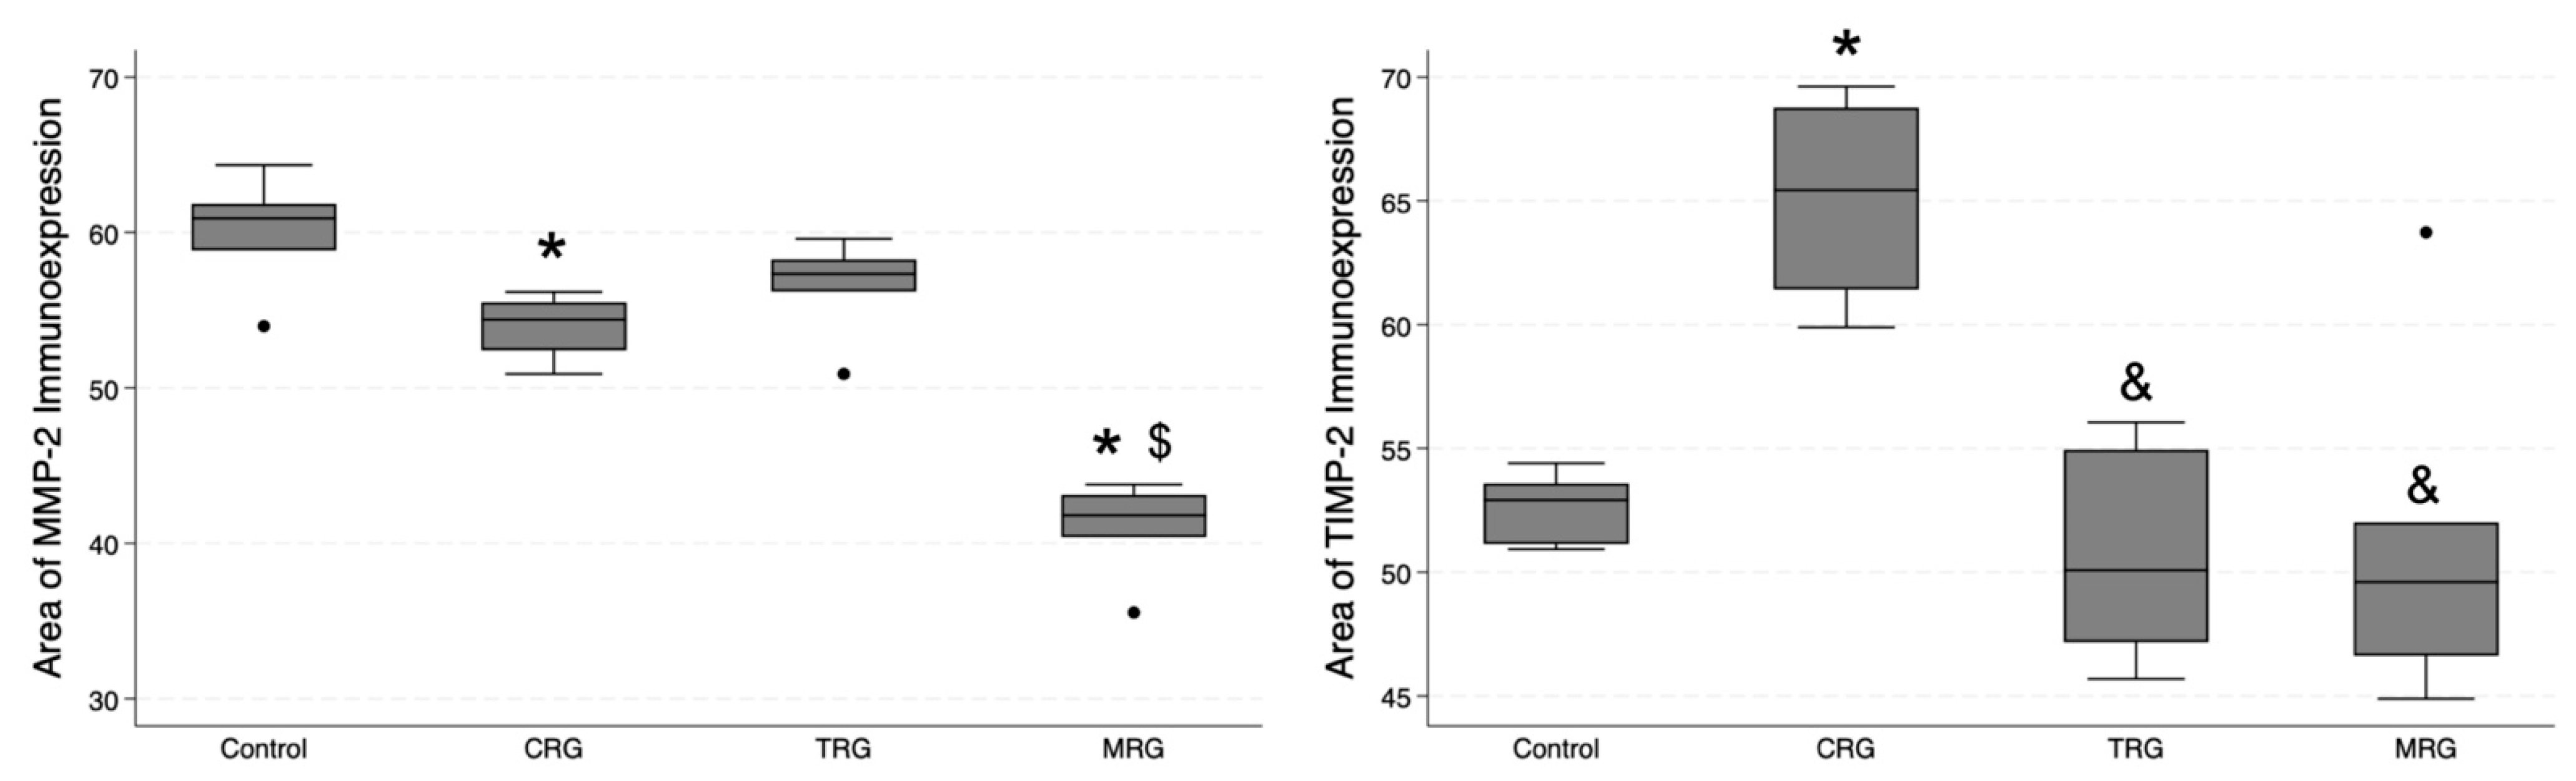

3.5. Digital Analysis of Immunolocalization of the MMP-2/TIMP-2

3.6. Digital Analysis of Immunolocalization of the MMP-9/TIMP-1

| MMP-2 area | 60.9 (58.85; 61.84) | 54.4 (52.42; 55.52) | 57.33 (56.21; 58.27) | 41.8 (40.41; 43.12) | 0.0009 | CRG: 0.0239 TRG: 0.1284 MRG: 0.0000 | 0.1674 | 0.0641 | 0.0027 |

| TIMP-2 area | 52.91 (51.14; 53.59) | 65.44 (61.43; 68.77) | 50.08 (47.18; 54.94) | 49.61 (46.63; 52.02) | 0.0214 | CRG: 0.0282 TRG: 0.2118 MRG: 0.1332 | 0.0043 | 0.0019 | 0.3778 |

| MMP-9 area | 55.18 (53.17; 56.53) | 53.06 (52.54; 53.32) | 53.49 (50.2; 57.85) | 41.31 (40.87; 42.89) | 0.004 | CRG: 0.2132 TRG: 0.2385 MRG: 0.0003 | 0.4368 | 0.0117 | 0.0033 |

| TIMP-1 area | 53.9 (51.49; 58.04) | 54.75 (51.53; 58.54) | 44.64 (40.71; 47.99) | 34.78 (33.4; 39.29) | 0.0005 | CRG: 0.5 TRG: 0.0131 MRG: 0.0001 | 0.0234 | 0.0006 | 0.0774 |